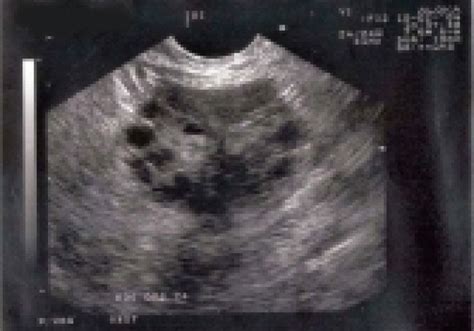

Het Polycysteus Ovarium Syndroom (PCOS) wordt gekenmerkt door de aanwezigheid van meerdere met vocht gevulde blaasjes in de eierstokken. Dit proces verstoort de rijping van de eiblaasjes en leidt vaak tot het uitblijven van de eisprong en daardoor weinig tot geen menstruatie.

Bij PCOS produceren vrouwen doorgaans te veel insuline, wat resulteert in een overproductie van androgenen. Deze hormonale disbalans verhindert de volledige rijping van de follikels en dus de eisprong. De diagnose kan gesteld worden met behulp van hormonale bepalingen en een vaginale echografie, waarbij micropolycystische eierstokken een karakteristiek beeld geven.